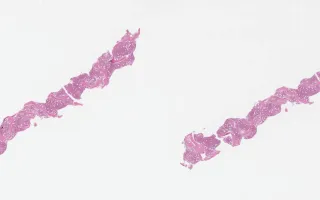

Bone Marrow, Gamma Heavy Chain Disease, H&E stain

Gamma heavy chain disease presents like lymphoplasmacytic lymphoma in the bone marrow but lacks light chain. The slides demonstrate the presence of a neoplastic plasma cell population. Monoclonal IgG is seen by immunohistochemistry. Clinically, immunofixation will demonstrate IgG without light chain in the blood and/or urine.

This slide shows bone marrow biopsy, H&E stain. See related content for peripheral blood, bone marrow aspirate, and IHC of bone marrow biopsies.